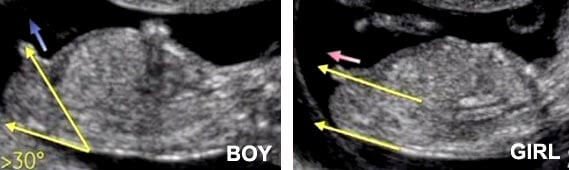

This is because the angle of the tubercle is increasingly gender-specific the further along you are. In essence, if the tubercle angle at 12-14 weeks is less than thirty degrees, the baby is likely a girl. If it is greater than thirty degrees, the child is likely a boy.

While the percentage of accuracy and positive results determined by nub theory is high, the procedure is not a simple one. For this method to be as reliable as possible, the sonographer must be able to adjust the baby’s position. This is because the so-called “angle of the dangle” is determined in relation to the baby’s spine, which needs to be relatively straight as compared to the pelvis.